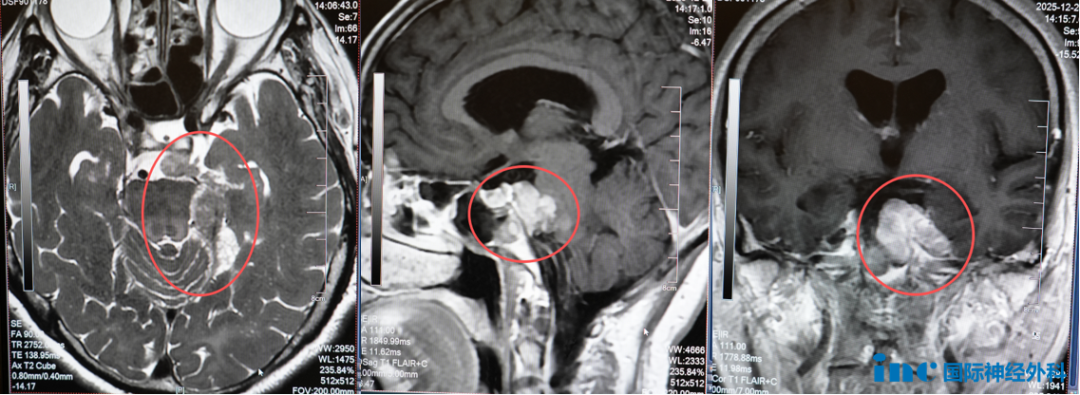

61岁女性患者鲁女士,2003年7月因左侧额部麻木疼痛、额纹消失,发现脑干三叉神经区脑膜瘤,行开颅手术后肿瘤残留,相继出现视物颠倒、复视,伽玛刀治疗后发生左侧肢体麻木、乏力。2012年复查提示脑膜瘤复发,行第二次伽玛刀治疗。2018年以来逐渐出现左侧耳鸣、左侧面部持续性麻木疼痛,2025年症状加剧。巴特朗菲教授表示手术将力争最大程度切除肿瘤,同时保护神经功能。

巴特朗菲教授仔细分析每位患者的影像学资料,结合具体临床表现和功能状态,以数据化、个体化的方式评估每例手术的可行性、风险程度和预期效果,为患者提供明确的治疗方向。